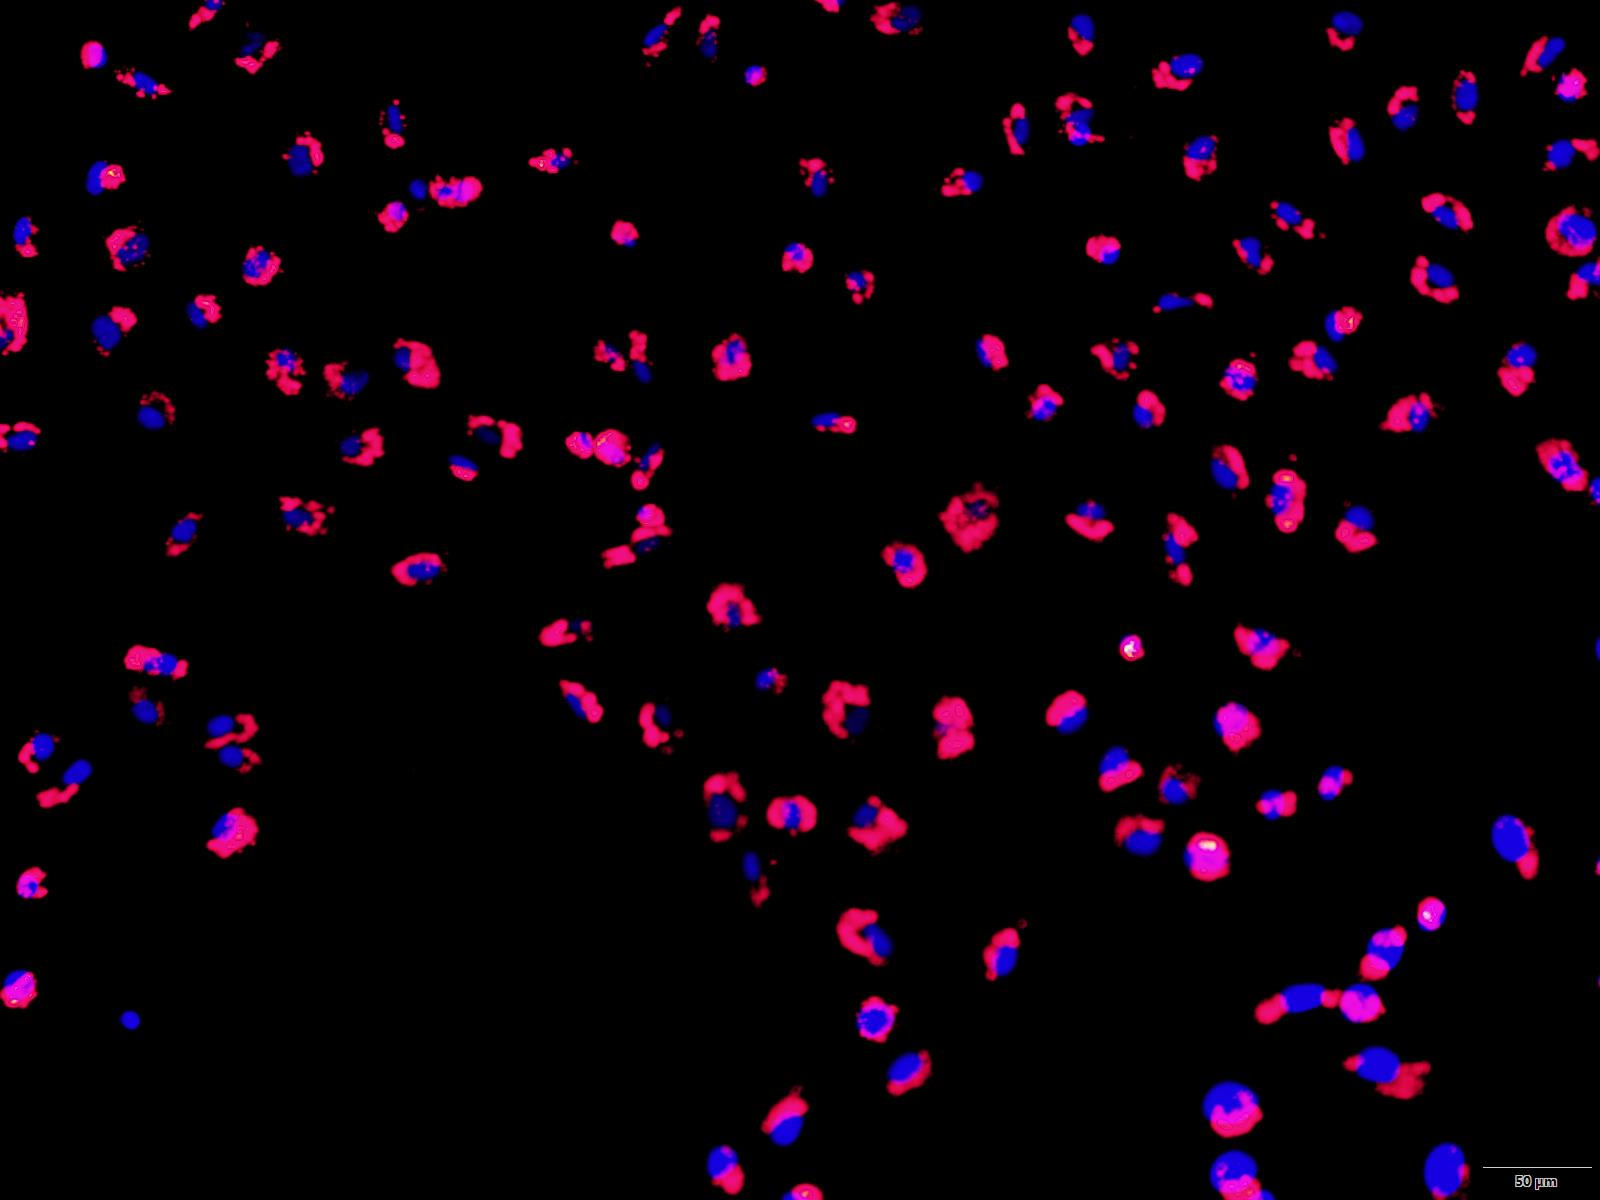

的细胞时,模拟流动状态显得尤其重要,如内皮细胞或上皮细胞。 下图实验显示了静态和流动状态下人脐静脉内皮细胞(HUVEC)的免疫荧光图像,显示在流体环境和静止环境下细胞的不同状态。 用鬼笔环肽(红色)染色细胞骨架 F-肌动蛋白。 VE-钙粘蛋白(绿色)标记粘附连接点。 使用 DAPI(蓝色)染色细胞核。上:HUVEC,静态培养,0 dyn / cm, 2.5 天, μ-slide 35mm 培养皿下:HUVEC,流体剪切力 10 dyn /cm²环境,2 天,μ-Slide I 0.4 Luer二